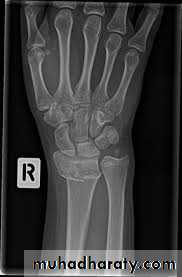

There is a transverse fracture of the radius at the corticocancellous junction, and often the ulnar styloid process is broken off. The radial fragment is impacted into radial and backward tilt. Sometimes there is an intra-articular fracture; sometimes it is severely comminuted.TREATMENT

3-IMPACTED OR COMMINUTED COLLES’ FRACTURESWith substantial impaction or comminution in osteoporotic bone, manipulation and plaster immobilization alone may be insufficient. The fracture can sometimes be reduced and held with percutaneous wires, but if impaction is severe even this may not be enough to maintain length; in that case, an external fixator is used to neutralize the compressive force of the 25 tendons crossing the wrist, and bone graft or bone substitute is placed into the gap. The fixator is attached to the distal radius and the second metacarpal shaft.

IMPACTED OR COMMINUTED COLLES’ FRACTURES